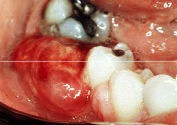

chronic hyperplastic pulpitis

-Red or pink nodule protruding from the pulp chamber or a tooth with a large open carious lesion (usually molars)